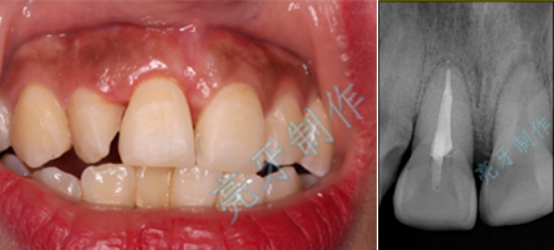

病例五:牙齿嵌入牙槽骨,牙龈撕裂,治疗后,恢复了自信和美丽的笑容。